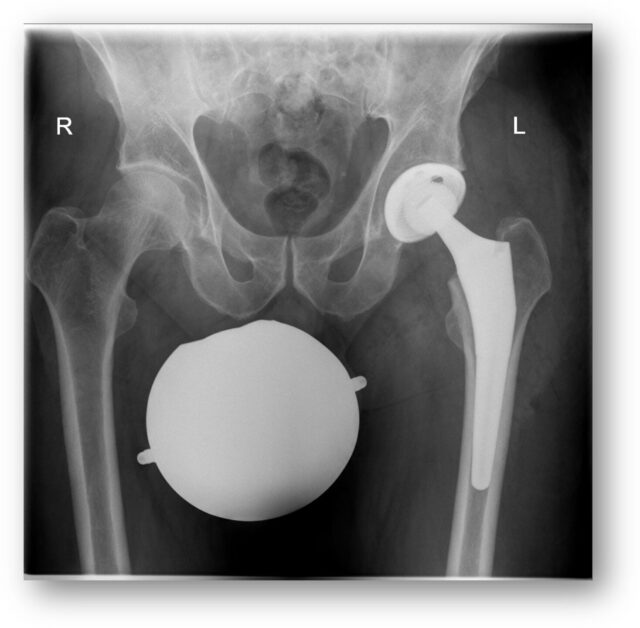

Moderne Hüft- und Knie-Endoprothetik: endlich wieder schmerzfrei und mobil

Arthrose ist eine Volkskrankheit: ab dem 65. Lebensjahr sind ein Drittel der Männer und etwa die Hälfte aller Frauen davon betroffen. Man versteht darunter eine fortgeschrittene Schädigung insbesondere des Gelenkknorpels, aber auch der umliegenden Gelenkstrukturen. Am häufigsten ist das Hüft- und Kniegelenk betroffen. Bei fortgeschrittener Arthrose kann die schützende Knorpelschicht auf dem Knochen komplett verschlissen sein – was für Betroffene nicht nur Schmerzen, sondern auch viele Funktionseinschränkungen im Alltag und beim Sport bedeutet.

Wenn alle konservativen Therapiemöglichkeiten ausgeschöpft sind und der Leidensdruck der Patient:innen hoch ist, kann gemeinsam die Indikation zur Operation gestellt werden. Moderne Prothesendesigns, minimal-invasive Zugangswege sowie eine intensive Betreuung der Patient:innen um die Operation herum, haben die Endoprothetik zu einem erfolgreichen und sicheren operativen Verfahren gemacht.

In seinem Vortrag erklärt der Arthrose-Spezialist, wie es zum Gelenkverschleiß kommt, welche Symptome bei fortgeschrittener Arthrose des Hüft- und Kniegelenks auftreten und wann ein operativer Eingriff sinnvoll sein kann. Unterschiedliche Operationsmethoden werden dargestellt, ein Überblick über die Zukunft der Arthrose-Behandlung rundet den Vortrag ab.